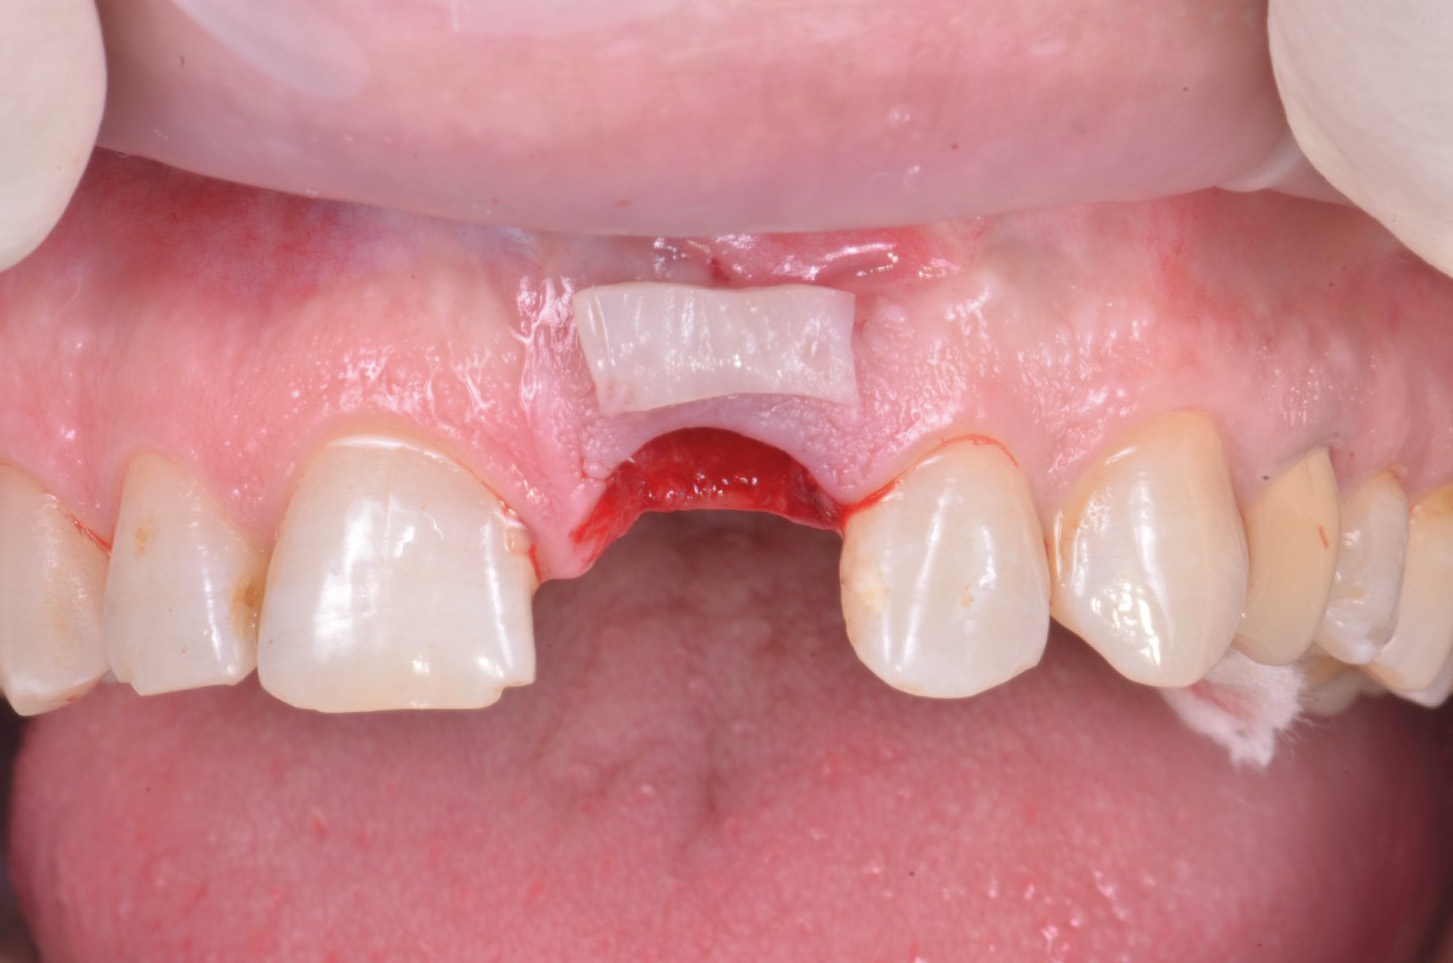

Un pilastro con vite dinamica è stato successivamente posizionato sul pilastro intermedio. Avendo optato per un inserimento post-estrattivo si è reso necessario compensare la “jumping distance” tra la parete vestibolare residua dell’alveolo e il corpo implantare e per questo è stato innestato osso bovino particolato deantigenato (Bioss, Gesitlich Biomaterials, Wollhousen, Svizzera). Successivamente sono stati gestiti i tessuti molli al fine di garantire un aspetto naturale del profilo esterno della cresta. Per questo è stato eseguito un prelievo epitelio-connettivale dal palato, successivamente de-epitelizzato, il quale è stato innestato “a busta” con un lembo a mezzo spessore con tecnica “a tunnel” sul versante vestibolare (fig.10,11).